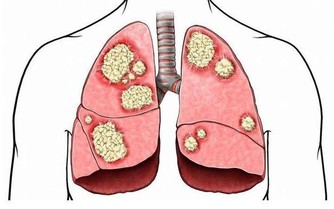

黃子慧說,乳腺結核病、乳腺癌患者經常會導致腋窩淋巴結腫大,

因此,如果是發現有腋窩淋巴結腫大,首先要排除這兩種病的可能。

另外如果出現無痛性腋窩淋巴結腫大,很可能是淋巴癌導致的。

如果出現異常反而不宜按摩刺激,應盡快就診。